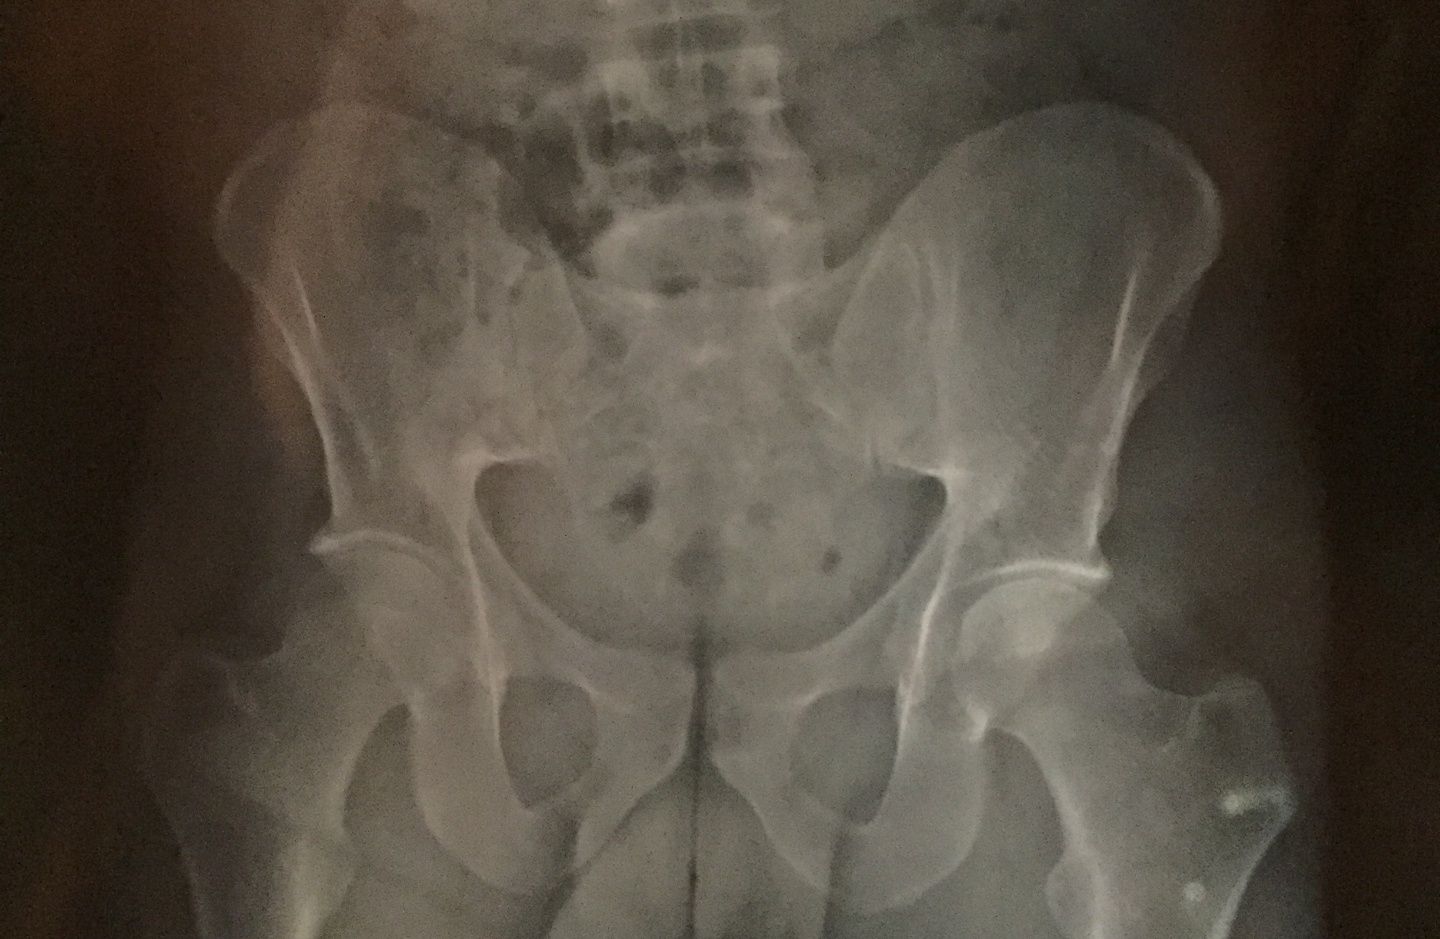

Le bassin, ou ceinture pelvienne, composé des os iliaques, du coccyx et du sacrum, est le socle de la colonne vertébrale et reçoit donc le poids de la partie supérieure du corps. Le bassin, s'articule également avec les fémurs formant l'articulation de la hanche. C’est donc une zone de transmission des pressions, soumis à de fortes contraintes, lors de la marche ou de la course à pied.

Les douleurs de hanche et du bassin sont très fréquentes dans la population sportive. Il faudra être vigilant et éliminer toute douleur projetée ou d'une autre origine que traumatique ou microtraumatique.